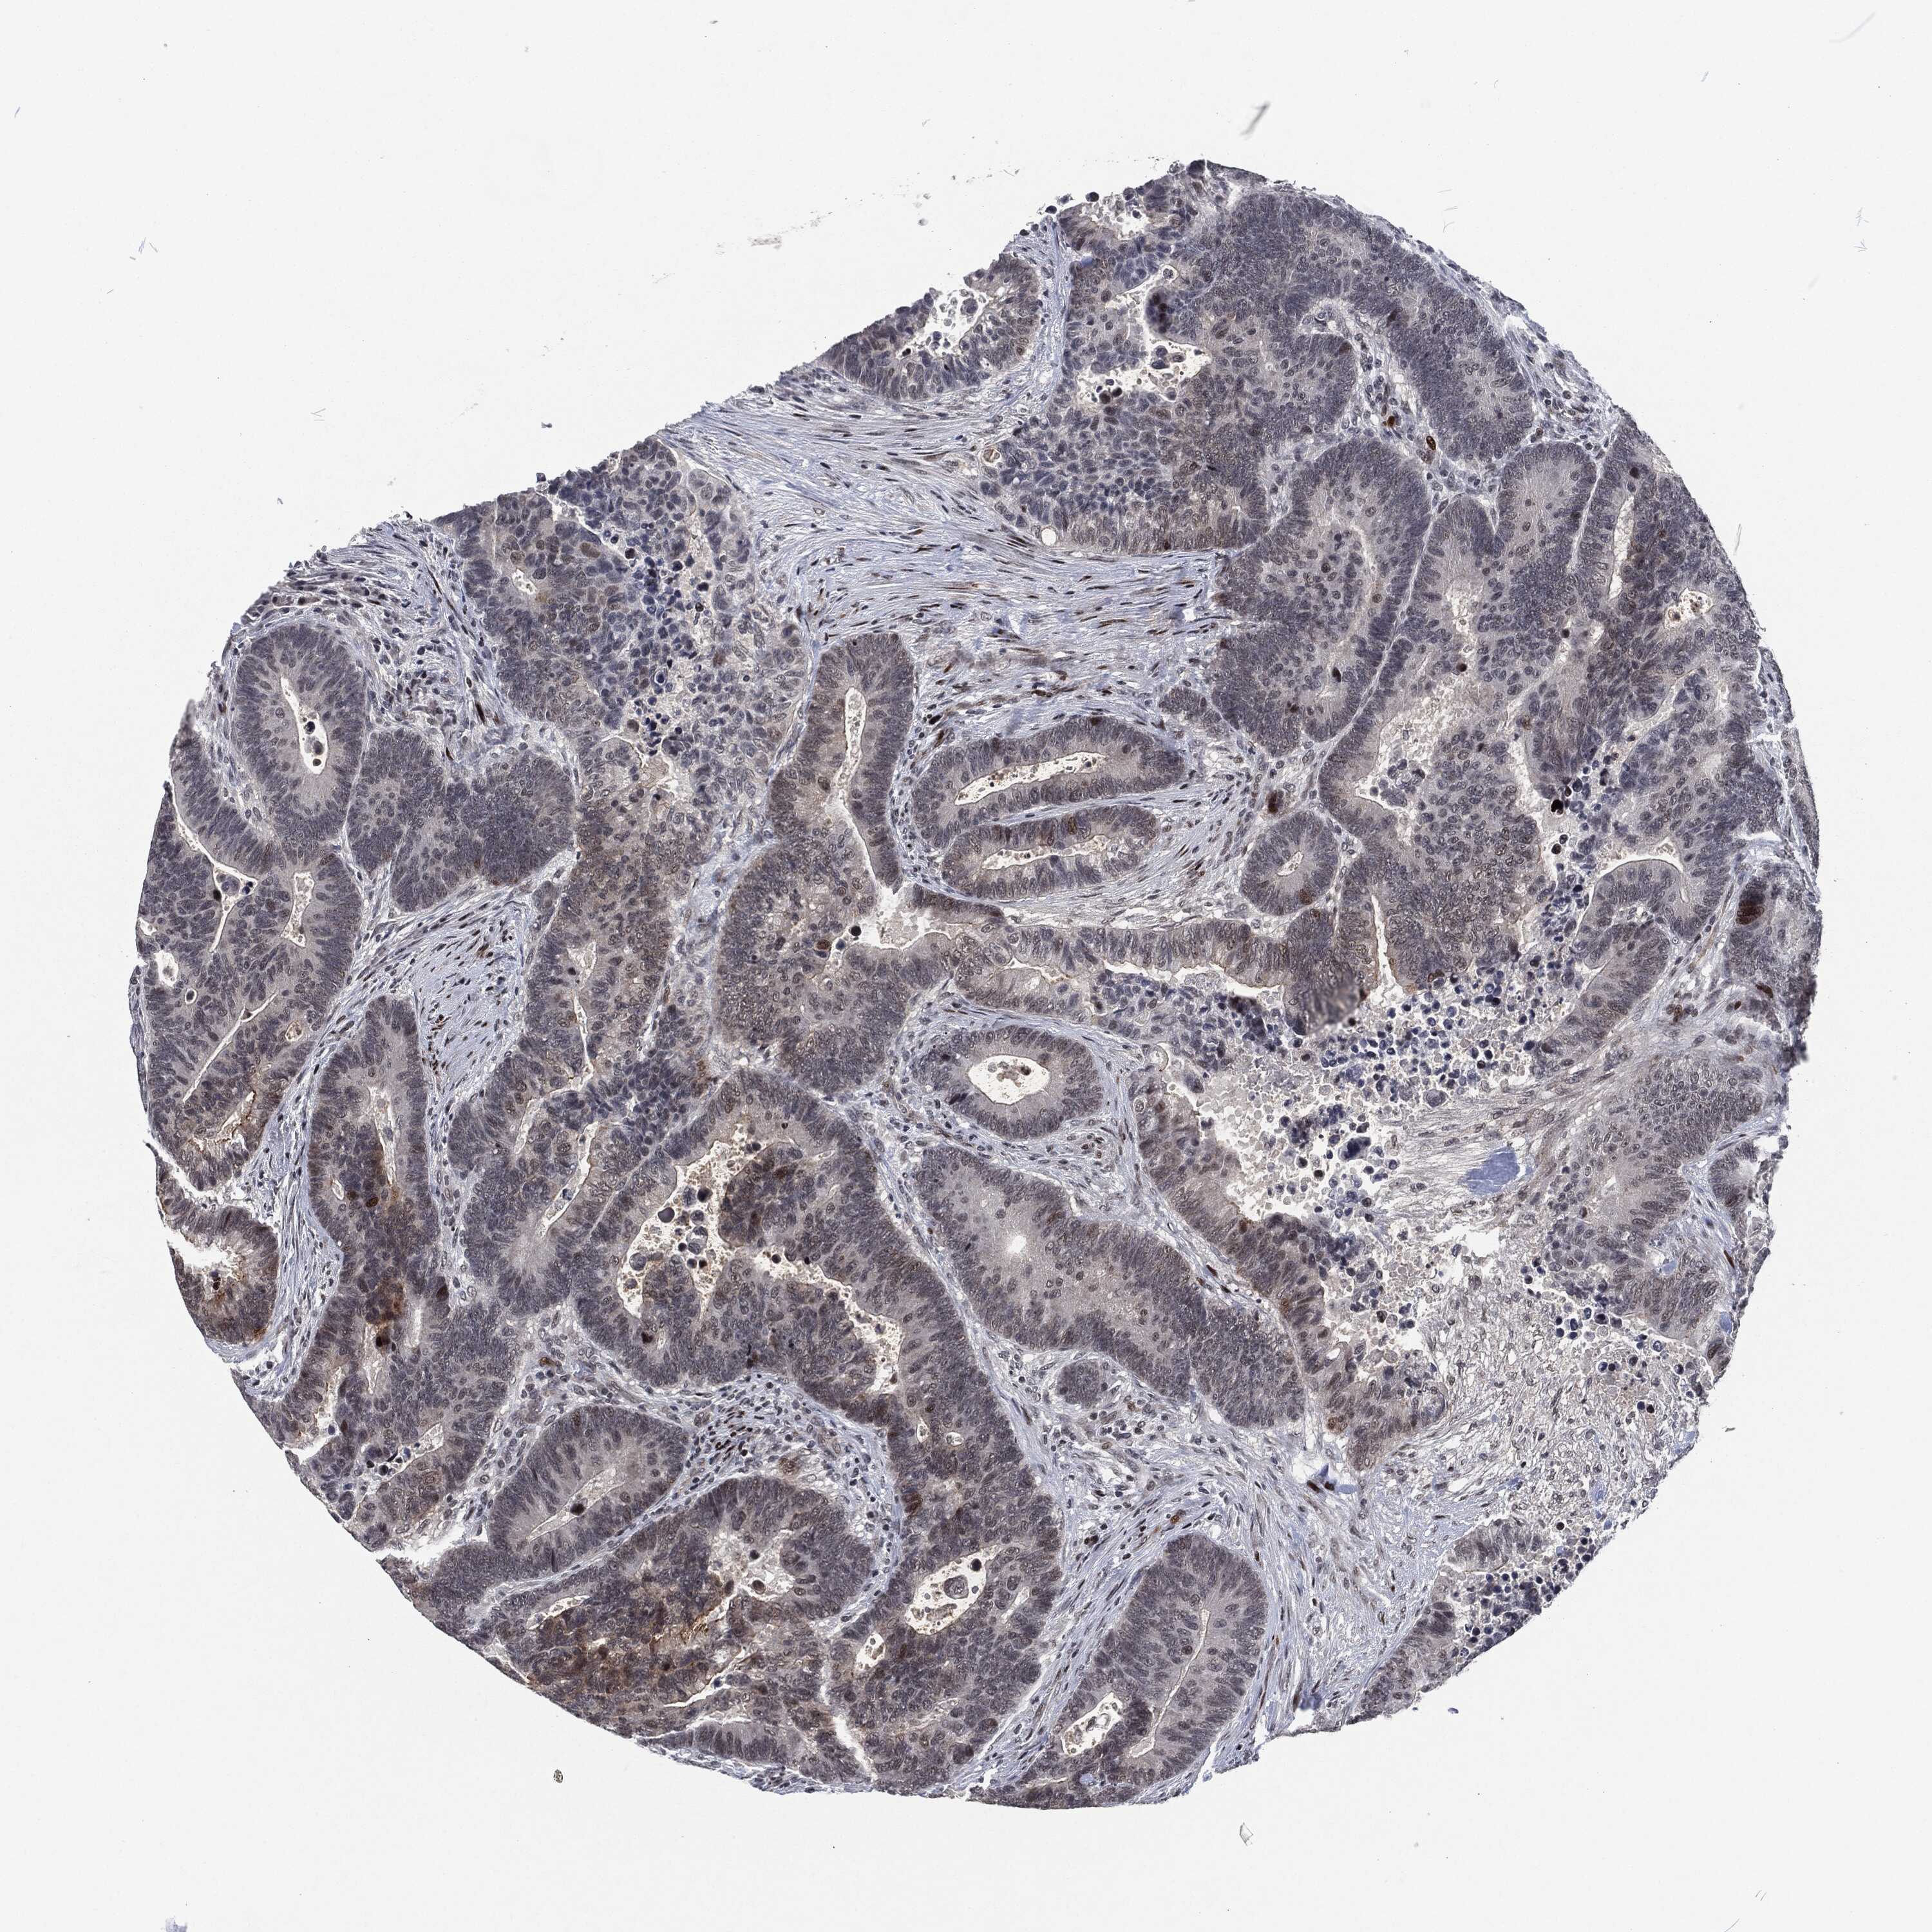

CANCER COLORECTAL CANCER Show tissue menu

Colorectal cancer

Human cancer

Rectum adenocarcinoma